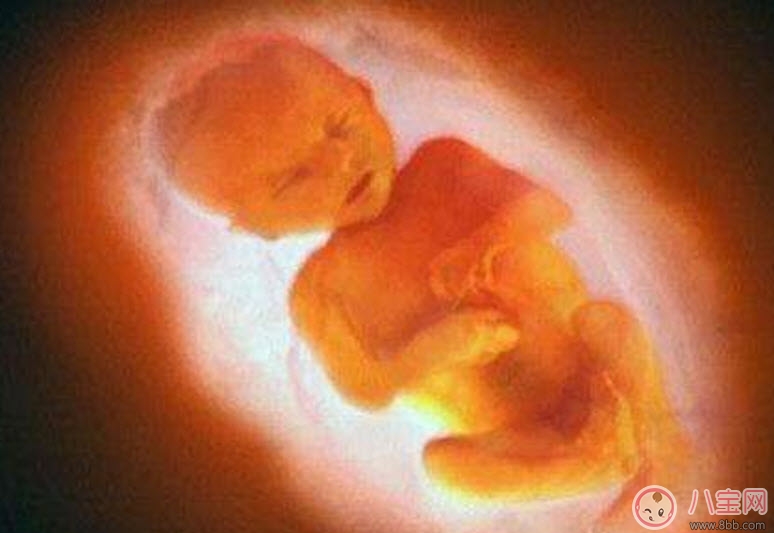

三維、四維超聲就是把很多個二維斷面圖像通過計算機重建成一個立體的圖像。相當于把切成很多片的西瓜,重新堆疊成一個完整的西瓜,這個堆疊過程由計算機完成。三維、四維的區(qū)別在于,三維是照片,四維是影片,四維就是會動的三維照片(實時三維)。

2、查看胎兒的活動:可以檢查到胎兒在宮內(nèi)是否缺氧,肢體運動、胎兒的吞咽動作等,能夠很好的看到胎兒在母體內(nèi)的活動狀況。

懷孕7個月左右也是做四維彩超檢查的好時機。這個時期的胎兒的皮下脂肪、面部表情都會比較飽滿、清晰。同時還可以看到胎兒在母體中的形體動作以及面部表情。這個階段的檢查對于胎兒的發(fā)育是否正??梢愿用鞔_。這對懷孕晚期的胎兒健康尤其重要,所以必須好好做詳細的檢查。